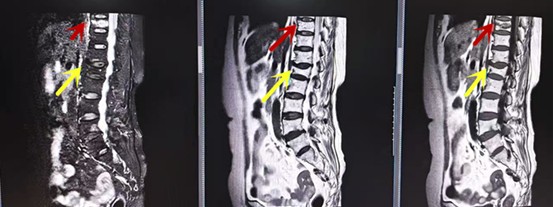

从左向右依次为CT矢状位重建图像、三维重建图像、轴位扫描图像,箭头提示腰1椎体爆裂性骨折

红色箭头提示新鲜骨折,黄色箭头提示陈旧性骨折